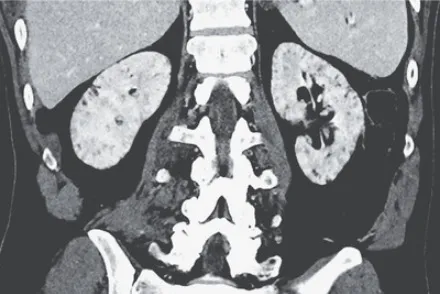

Microcistos renais e lítio: existe relação? O uso crônico de lítio pode impactar os rins, mas qual o papel dele na formação de microcistos renais? Entenda o que a literatura recente revela.